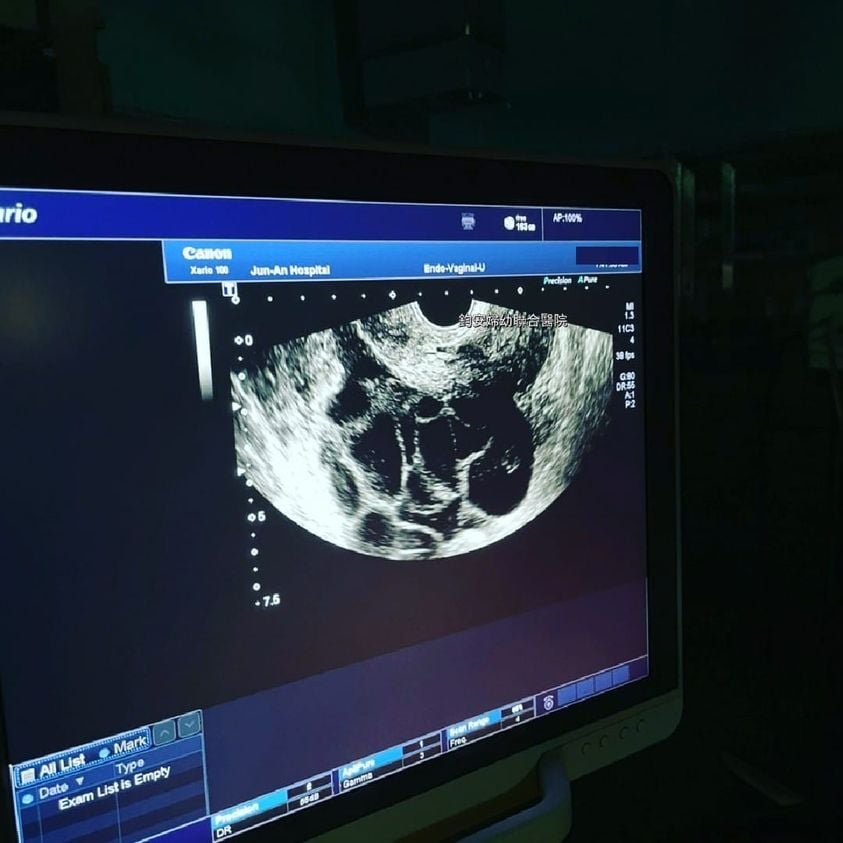

生殖醫學不孕症

不孕症檢查-女性篇

了解不孕因素

認識不孕症